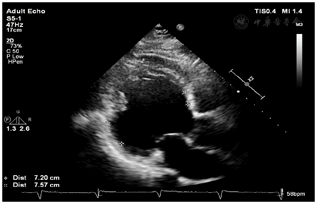

在考虑使用靶向生物制剂之前,我们决定再次对该患者进行多维评估,特别是共病的筛查。完善心肌标志物、心脏彩超、MRI心脏功能(图4,图5)增强扫描并请心内科专家阅片及评估后考虑诊断"扩张型心肌病、心功能Ⅲ级",予以双腔ICD置入术,同时行强心、利尿、抑制心室重构等对症治疗,哮喘方面我们也成功将激素减量至信必可80 µg/4.5 µg 1揿,2次/ d单药吸入治疗。